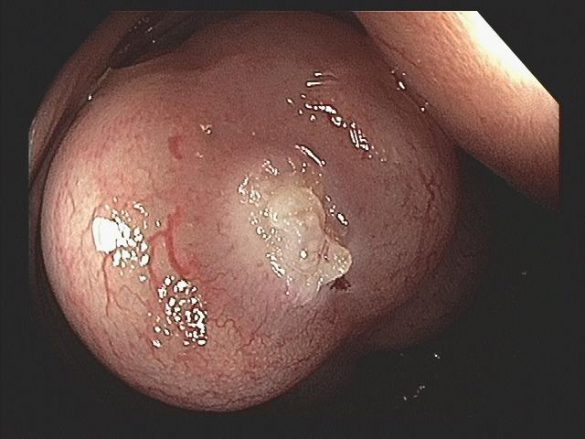

A PI pode afetar o intestino delgado, cólon ou ambos. Os cistos podem estar confinados à mucosa, submucosa ou subserosa, ou envolver todas as três camadas. Cistos subserosos são mais comumente vistos na pneumatose do intestino delgado, enquanto os cistos submucosos são mais comumente vistos na pneumatose cólica (como no caso em questão).

A PI pode ser descoberta incidentalmente na colonoscopia e deve-se prosseguir a investigação com ultrassonografia endoscópica. Cistos variam em tamanho de alguns milímetros a vários centímetros. Os cistos da submucosa costumam ter uma aparência pálida ou azulada e, quando biopsiados, podem desinflar rapidamente com um chiado audível.